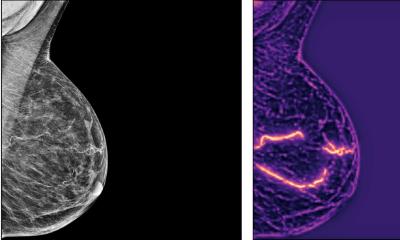

‘Two-for-one’ screening uses mammograms to predict heart disease in women

Using AI to help detect one of the leading killers of women worldwide: A new machine learning model can successfully predict heart disease risk in women by analysing mammograms.